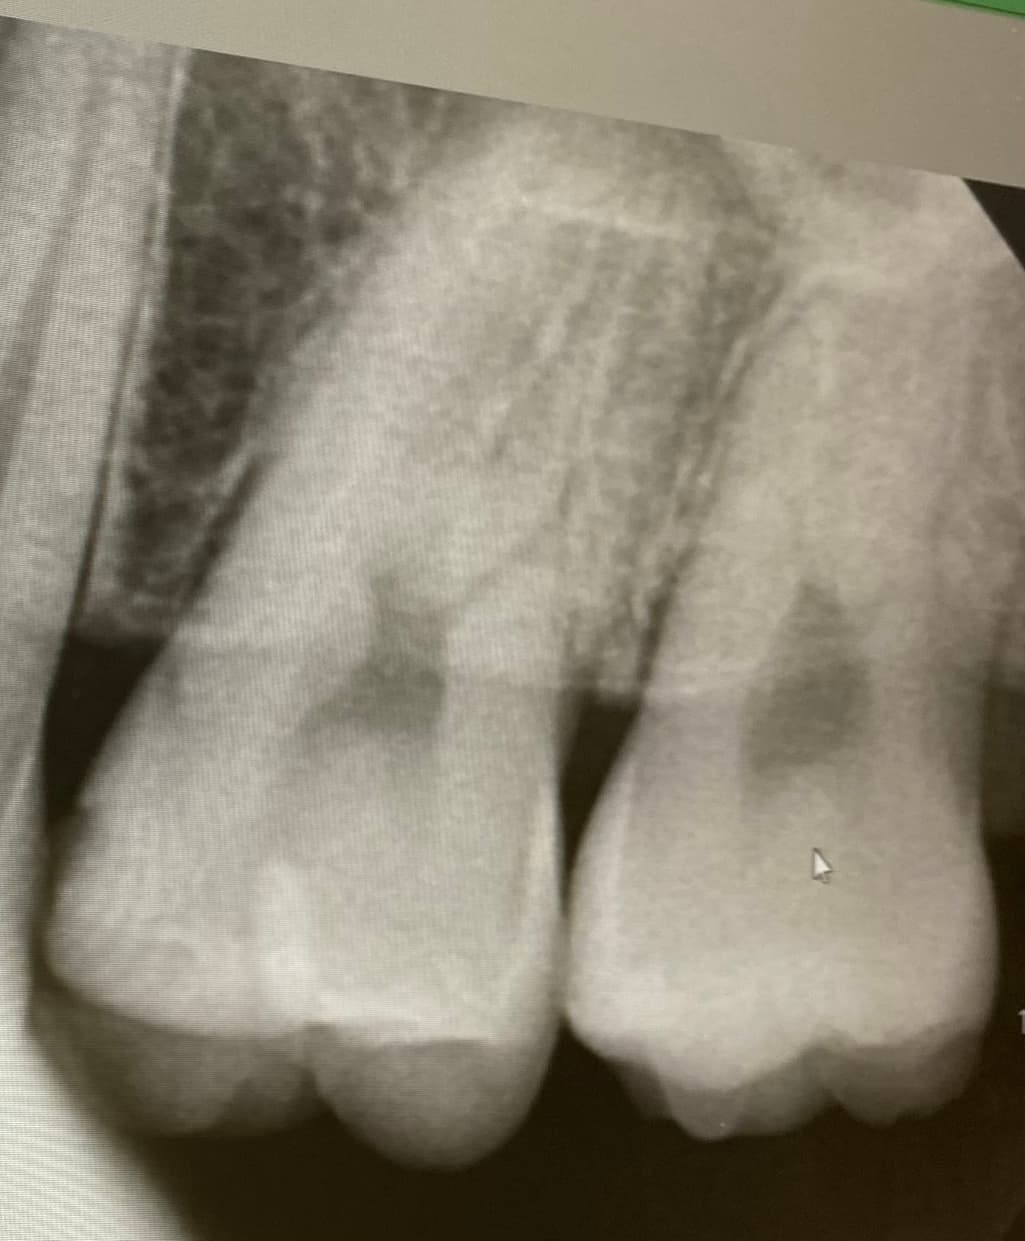

1치과는 충치가 있는 것 같다 양 옆 색상 차이가 있다 눈으로 확인 되는 정도라면 치료 해야 할 시기이다

위치 왼쪽 위 2번째 어금니 치료 한 부위 2차 충치

사진에 보이는 정도면 충치가 안쪽에 많이 진행됫을 가능성이 있습니다. 저라면 인레이로 치료를 할것같습니다.

육안으로 보였을 경우 인절면에 충치가 있는 것으로 보입니다. 하지만 방사선상에는 크게 보이진 않습니다. 눈으로 보이는 충치가 있기 때문에 인접면 충치는 치료를 하는 것이 좋을 것으로 생각됩니다.